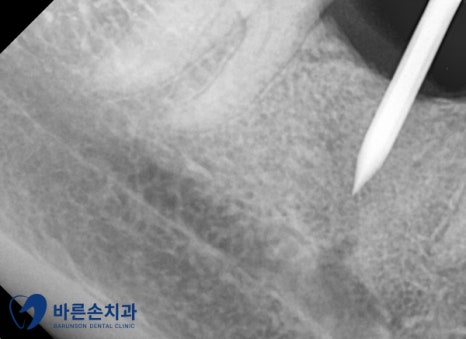

임플란트를 식립 하였습니다.

CT를 찍어 임플란트가 잘 심어졌는지

확인 후 수술을 마무리 하였습니다.